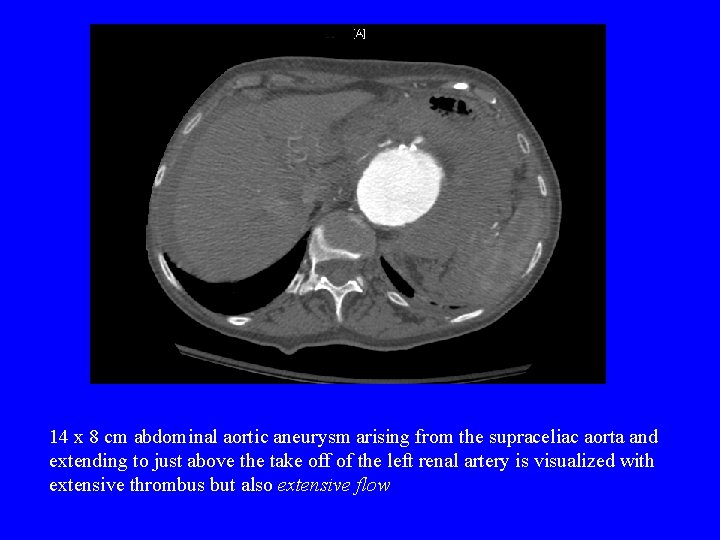

14 x 8 cm abdominal aortic aneurysm arising from the supraceliac aorta and extending to just above the take off of the left renal artery is visualized with extensive thrombus but also extensive flow

Diagnosis Imaging • Plain Films – Enlarged outline of calcified aortic wall • A retrospective review showed that 65% of x-rays form RAAA had calcified aortic wall – Loss of psoas shadow • Abdominal U/S – Sensitive in detecting aneurysm but not in detecting rupture • Abdominal CT – Most accurate method – See presence of retroperitoneal blood (77% sensitive and 100% specific)

See presence of retroperitoneal blood. Here there is not a large retroperitoneal hematoma, but stranding of blood into surrounding tissues